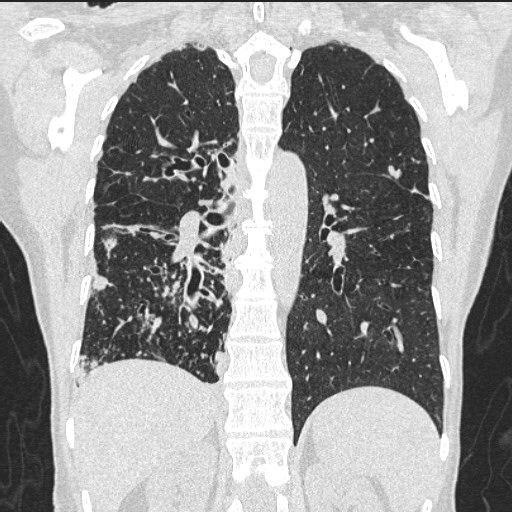

Chest Ct Bronchiectasis . A distinct feature of bronchiectasis is the tendency toward exacerbations. Furthermore, we developed a set of consensus statements concerning the definitions of clinical bronchiectasis and its. We prioritised criteria for the radiological diagnosis of bronchiectasis and suggest recommendations on the use and central reading of chest ct scans to confirm the presence of bronchiectasis for clinical trials. May be normal or may show. Chest radiography is usually the initial study performed in suspected bronchiectasis. A radiologist will associate bronchiectasis with the typical chest computed tomography (ct) scan features, consisting of an abnormally widened and thickened airway with an irregular wall, lack of tapering and/or visibility of the airway in the periphery of the lung [2]. Chest imaging, specifically ct scanning, is required to make the diagnosis of bronchiectasis.

Chest Ct Bronchiectasis Chest imaging, specifically ct scanning, is required to make the diagnosis of bronchiectasis. Furthermore, we developed a set of consensus statements concerning the definitions of clinical bronchiectasis and its. We prioritised criteria for the radiological diagnosis of bronchiectasis and suggest recommendations on the use and central reading of chest ct scans to confirm the presence of bronchiectasis for clinical trials. A distinct feature of bronchiectasis is the tendency toward exacerbations. Chest radiography is usually the initial study performed in suspected bronchiectasis. May be normal or may show. A radiologist will associate bronchiectasis with the typical chest computed tomography (ct) scan features, consisting of an abnormally widened and thickened airway with an irregular wall, lack of tapering and/or visibility of the airway in the periphery of the lung [2]. Chest imaging, specifically ct scanning, is required to make the diagnosis of bronchiectasis.